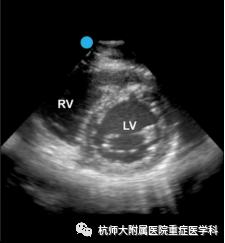

b.胸骨旁短轴切面:位置选择:胸骨左缘第2~5肋间,超声探头标记点指向左肩;操作过程中在获得胸骨旁左心室长轴平面后,将二尖瓣调整至屏幕中央,超声探头顺时针旋转约90°,使超声探头标记点朝向左肩可获得二尖瓣水平短轴切面。将超声探头尾部向心底倾斜,超声探头声束向心尖倾斜,可依次获得胸骨旁左心室短轴乳头肌平面和心尖平面。

主要评估内容:(1)左心室收缩功能定性评估及分级;(2)左心室壁节段运动障碍;(3)右心形态改变;(4)室间隔运动评估;(5)评估室间隔缺损的最佳切面。